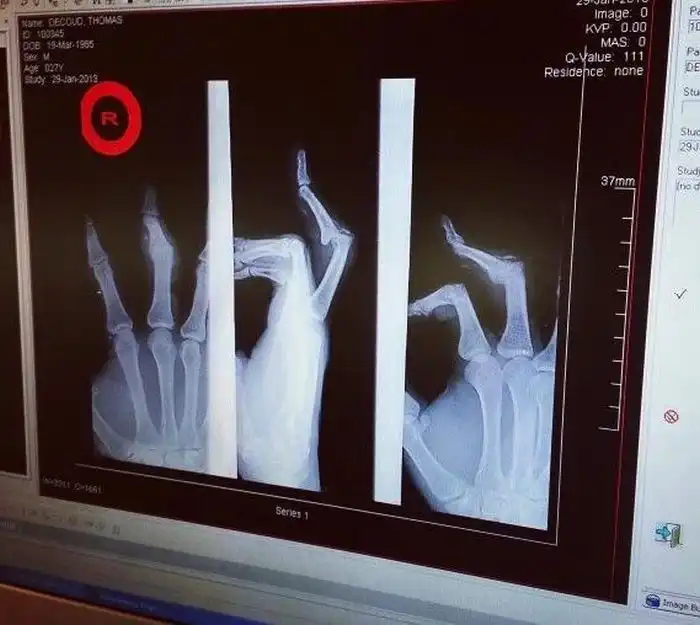

Томас ДеКуд: игрок в американский футбол